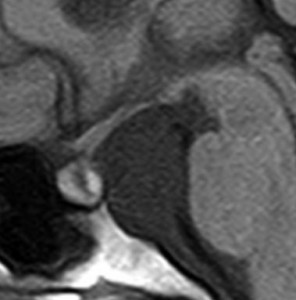

5歳の時に発見され23歳まで18年間経過観察をされてきた患者さんです。腫瘍はゆっくり,しかし確実に増大して,手術前には頭痛がひどく薬も効かず歩けなくなったという症状でした。術後に頭痛が無くなったので,のう胞による症状だったのでしょう。

下垂体柄の周囲にのう胞性腫瘍があります。T1強調画像では等信号,T2強調画像ではまだらな信号になっています。23年という長い経過から液状内容物が固形化したものと推定されます。T2で低信号となる部分があるのですが,黄色肉芽腫とは異なる像です。

下垂体柄は長く伸びています。のう胞による長期の圧迫のため斜台上部がerosionになって凹んでいます。トルコ鞍内の中間葉の位置に典型的な小さなラトケのう胞(黄色矢印)がみられますが,これは長年変化していませんでした。

左前頭側頭開頭 pterional approachで,のう胞壁を含めて完全摘出 complete removalしました。のう胞は下垂体柄の左側に付着してそこから発生したものでした。内容物は固体で寒天状のコロイドでした,一部軟らかくて一部は線維化していました。のう胞壁は半透明で薄い部分も線維性の膜状の部分もありました。病理検査では上皮細胞が証明されて内胚葉のう胞 endodermal cystの診断です。

ラトケのう胞はhiatusから内容液吸引だけして,皮膜はもちろんそのままにしています。